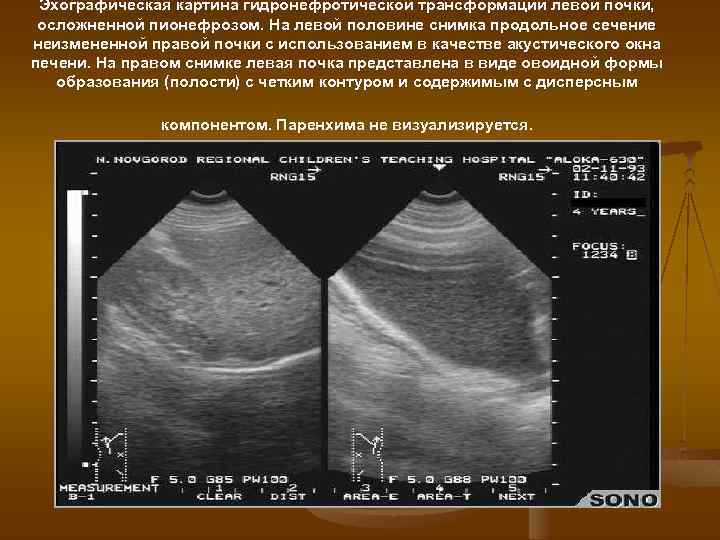

Эхографическая картина гидронефротической трансформации левой почки, осложненной пионефрозом. На левой половине снимка продольное сечение неизмененной правой почки с использованием в качестве акустического окна печени. На правом снимке левая почка представлена в виде овоидной формы образования (полости) с четким контуром и содержимым с дисперсным компонентом. Паренхима не визуализируется.